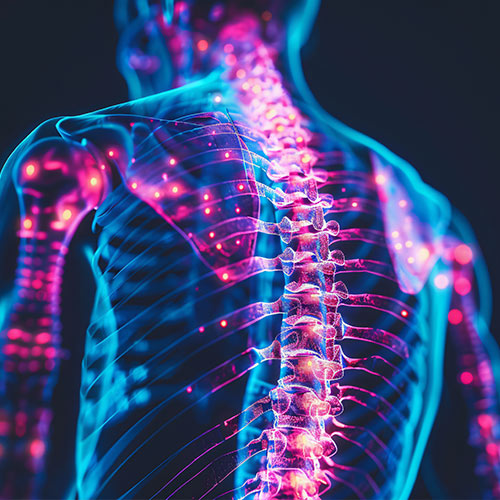

Spinal Canal Stenosis is a condition where the space within the spinal canal narrows, putting pressure...

Cervical Spinal Canal Stenosis is a condition where the spinal canal in the neck narrows, putting pressure...